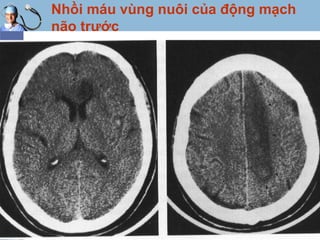

Nhồi máu vùng nuôi của động mạch

não trước

www.themegallery.com